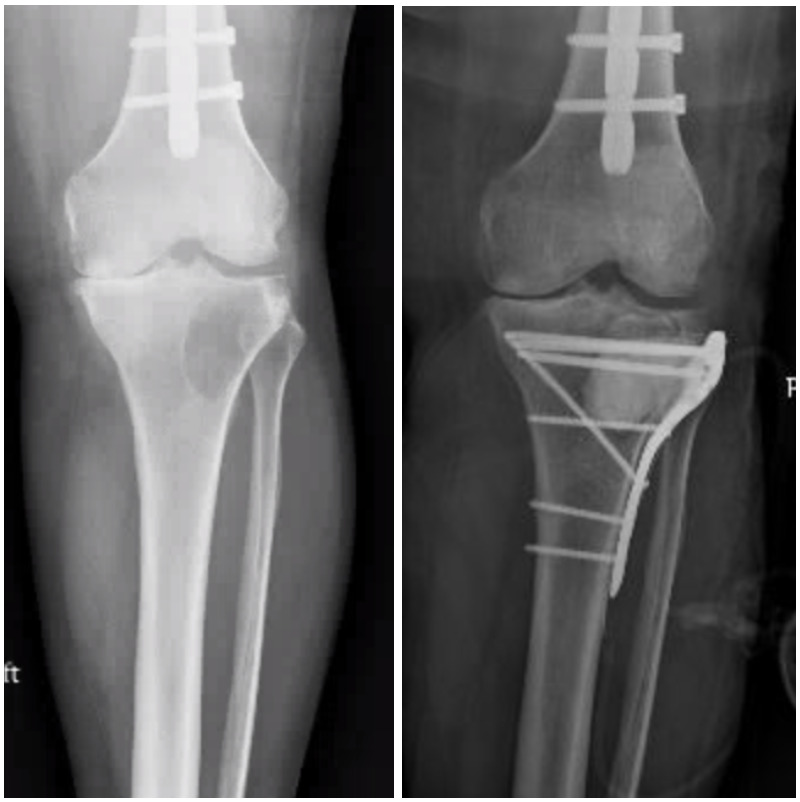

Acral metastases, defined as lesions distal to the elbow and knee, are often encountered in cases of advanced metastatic carcinoma and tend to be, therefore, associated with limited patient survival.101 Sixty-eight percent of acral metastases are to the tibia, and the tibia is the third most common long bone overall to develop metastatic disease.102,103 Often, these lesions can be treated effectively with palliative radiation.2,104 Locked plating with cement augmentation is commonly used when surgery is indicated in periarticular locations such as the tibial plateau and plafond [Figure 6]. The subcutaneous nature of these anatomic locations introduces considerable wound complications and infection risk, which are reported at 12% by Bonnevialle et al. For skeletal metastases within the metadiaphyseal or diaphyseal tibia, intramedullary nailing provides relatively simple stabilization, achieving pain relief and restoring ambulatory function.104 Post-operative radiotherapy is critical to minimizing the local progression of disease. Due to primarily compression forces in the tibia as compared to tensile forces that exist in the proximal femur, mechanical failure of tibial constructs is a less frequent complication.101